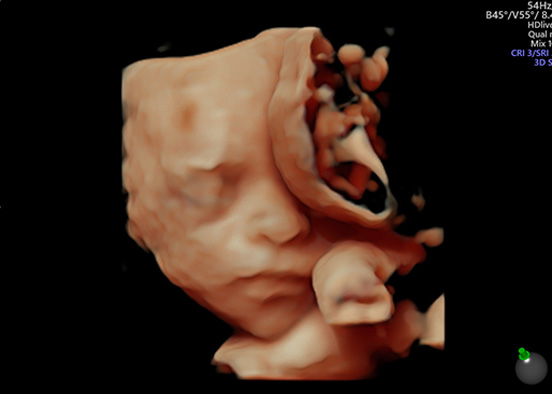

Nuestros estudios están diseñados para acompañarte en cada etapa del embarazo, desde la translucencia nucal hasta la evaluación del crecimiento fetal en el tercer trimestre. Cada ultrasonido busca identificar alteraciones estructurales, cromosómicas y monitorear el desarrollo del bebé.

En Amal’nai ofrecemos ultrasonidos materno fetales de alta especialidad, fundamentales para cuidar el bienestar de tu bebé desde el inicio del embarazo. Cada estudio está indicado en una etapa específica y cumple con protocolos internacionales para la detección oportuna de alteraciones estructurales o cromosómicas, así como para la vigilancia del flujo sanguíneo fetal y uterino.